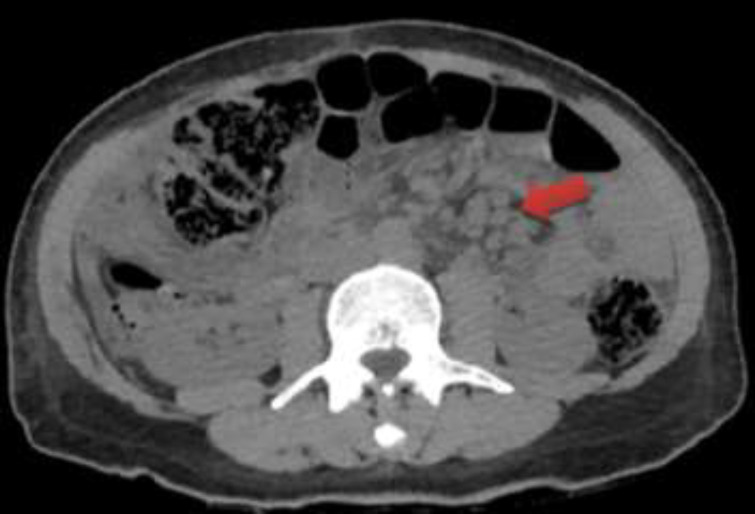

Case presentation: Herein, we present a Persian male adult who manifested with epigastric pain, weakness, and a history of pleuritic chest pain two months prior to admission. The findings of the physical examination included vital signs within the normal range, unilateral fine crackle in the lung, abdominal distension with positive shifting dullness, and fluid wave test. Analysis of the ascitic fluid revealed a Serum-ascites albumin gradient (SAAG) of less than 1.1g/dl, indicating a non-portal condition. The results of the acid-fast bacilli (AFB) staining as well as the TB polymerase chain reaction (PCR) test were negative. However, the adenosine deaminase (ADA) level was 44 IU/L. A chest CT scan revealed mediastinal lymph node enlargement and pleural thickening with loculated pleural effusion. Three acid-fast bacilli smear of morning sputum were sent, and all three were negative. An abdominopelvic CT scan showed multiple periaortic and mesenteric lymph nodes of varying sizes with mesenteric haziness and accumulation of effusion in the peritoneal cavity. Eventually, peritoneal biopsy, the gold standard, was performed, which revealed multiple granulomatous lesions and areas of caseous necrosis surrounded by Langerhans giant cells and epithelioid cells.